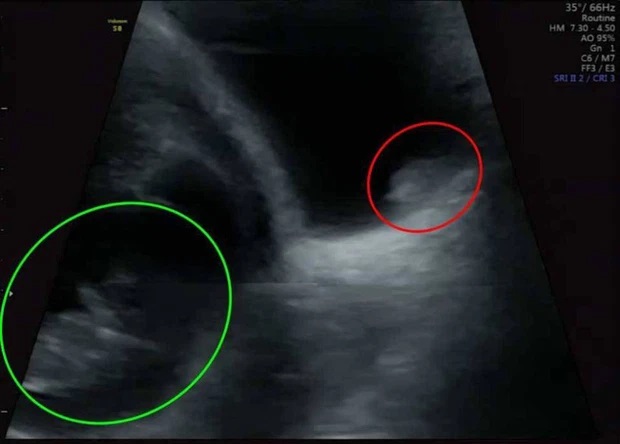

Yasmin kể: "Một vài tháng trước đó, tôi đã mang thai ngoài tử cung, nơi phôi thai được cấy vào phần tử cung không đúng. Lần này, tôi đã chủ động đi siêu âm ở tuần thứ 6 tại bệnh viện địa phương để kiểm tra thai có nằm đúng vị trí không, Carl và tôi muốn yên tâm thêm. Bác sĩ siêu âm cho biết em bé của chúng tôi trông rất ổn, cả hai chúng tôi đều rất hồi hộp khi được cảm nhận rằng trái tim nhỏ bé của con đang đập.

Vui mừng quá đỗi nên chúng tôi còn chẳng để ý bác sĩ đang tiếp tục dò máy và phát hiện 'vật thể lạ' trong bụng tôi".

Đi siêu âm thai, bà mẹ Yasmin phát hiện khối u trong bàng quang

Niềm vui ngắn chẳng tày gang, hóa ra "vật thể lạ" đó chính là khối u bàng quang.

"Khi cô ấy thông báo rằng có khối u trong bàng quang, cả 2 vợ chồng tôi đều sốc. Tôi vẫn chưa hình dung được mức độ nghiêm trọng về sức khỏe của mình", Yasmin nói.

Carl nói: "Tôi đã cố trấn an cô ấy rằng không có chuyện gì xảy ra và cả hai chúng tôi đều cố gắng tập trung vào việc có con. Nhưng khi chuyên gia tư vấn nói rằng chắc chắn có một khối u kích thước khoảng 2 centimet ở đó, chúng tôi đã hoàn toàn suy sụp".